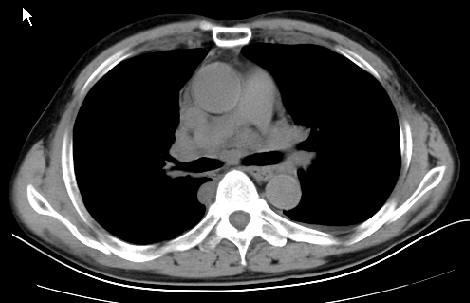

以下是引用草之原在2009-5-2 19:29:00的发言:[br]1.考虑右侧中心型肺ca纵膈淋巴结转移,双侧胸腔积液及右侧叶间裂积液,心包积液。[br]2.两肺上叶病灶,纵膈窗显示部分病灶硬化,考虑:结核。[br][br] [br]

以下是引用ct诊断高手在2009-5-2 19:08:00的发言:[br]我考虑右侧中央型肺癌 伴右肺节段性不张,两肺及纵隔淋巴结转移,右侧胸腔积液。

以下是引用zjzjr在2009-5-2 20:16:00的发言:[br]肺结核,转移瘤.纵隔淋巴结转移或淋巴瘤,右侧包裹性积液、斜裂积液。心包积液。